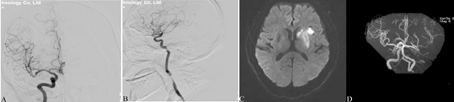

病例1:男性,68岁,因"头晕3 h,突发意识不清、四肢无力2 h"于2015年12月10日入院。患者于当日早7时静坐时出现头晕,视物旋转,恶心、呕吐,非喷射性呕吐非咖啡色胃内容物2次,觉右手麻木,未用药。1 h后突发意识不清、四肢无力,不能言语,立即被急诊送入院。头颅CT提示脑白质疏松,右侧基底节区腔隙性脑梗死。随后收入神经内科。患者6年前因"喉癌(鳞状细胞癌)"行"喉水平部分切除及双侧颈淋巴结清扫术",术后1个月给予放射治疗29次,总剂量60 Gy,未化疗。有高血压史2年,血压最高190/100 mmHg(1 mmHg=0.133 kPa),不规律用药,血压波动于140~160/80~90 mmHg。1年前出现气管塌陷,偶有憋气症状。入院查体:双眼垂直眼球震颤,右侧中枢性面瘫,右侧上肢肌力2级,余肢体肌力3级,四肢肌张力低,双侧病理征阳性。美国国立卫生研究院卒中量表(National Institutes of Health Stroke Scale, NIHSS)评分15分。入院诊断:(1)急性缺血性卒中;(2)高血压病3级;(3)喉癌术后。治疗经过和病情演变:因患者梗死症状较重,发病时间3 h,给予标准剂量阿替普酶静脉溶栓。溶栓过程中症状逐渐改善,眼球震颤消失,右侧中枢性面舌瘫,左侧肢体肌力恢复正常,右上肢肌力2级,右下肢肌力3级。溶栓后桥接脑血管造影+血管内机械血栓切除术,造影可见左侧颈内动脉闭塞,左侧颈外动脉通过眼动脉向颅内代偿,右侧颈内动脉起始段重度狭窄,远端血流充盈良好,左侧椎动脉优势供血,基底动脉及双侧大脑后动脉显影良好(图1A、图1B)。溶栓后24 h颅脑MRI示左侧大脑中动脉供血区多发点片状T1低信号、T2高信号、弥散加权成像高信号和表观弥散系数图低信号病灶,考虑为急性梗死灶,左侧颈内动脉及大脑中动脉闭塞可能(图1C、图1D)。给予阿司匹林(0.1 g/d)和氯吡格雷(75 mg/d)双联抗血小板治疗,阿托伐他汀(40 mg/d)降脂抗氧化,症状于2周内逐渐改善。出院时查体:神志清楚,言语流利,无眼球震颤,右侧中枢性面舌瘫,四肢肌力、肌张力、感觉、共济运动正常,双侧病理征阳性。最终诊断:(1)急性缺血性卒中(左侧大脑中动脉供血区);(2)高血压病3级;(3)放射性脑血管病(左侧颈内动脉闭塞,右侧颈内动脉重度狭窄);(4)喉癌术后。建议1个月后行右侧颈内动脉起始段支架置入术,患者因自身气管病变较重而拒绝。予阿司匹林(0.1 g/d)和氯吡格雷(75 mg/d)口服3个月,阿托伐他汀(40 mg/d)口服1个月。而后调整药物,长期口服阿司匹林(0.1 g/d)和阿托伐他汀(20 mg/d),门诊随访1年未再出现卒中事件。

A、B:左侧颈内动脉闭塞,右侧颈内动脉起始段重度狭窄;C:左侧基底节区急性期梗死灶;D:左侧颈内动脉闭塞